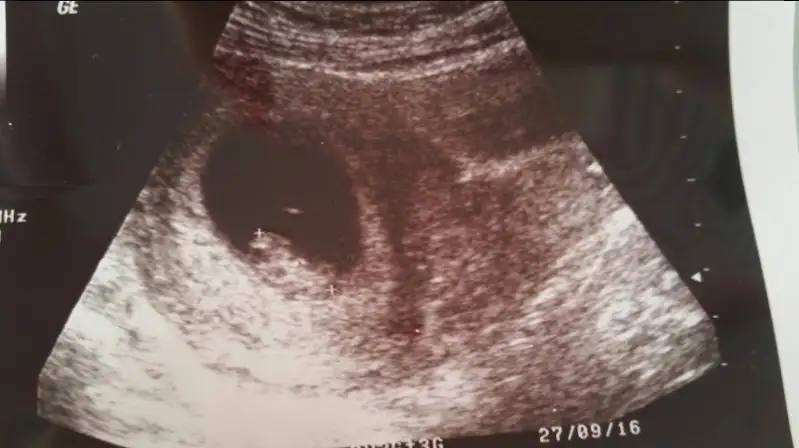

Kizlar benim simdi bebek daha buyuk ama bu ilk ultrasyondaki görüntü karindan tahminleriniz nedir acaba

İlk bebişin mi canım. Ben doktoruma direkt sordum. karından ultrasonda plasentasi solda görünüyorsa gerçekte sagda imiş. Usg vajinal ise plasenta diyelim ki solda görünüyor gerçekte de solda imiş. Bende bu teori tutmadı canım. Ama tutan çok fazla hamile var. Benim iki oglumunda plasentasi soldaydı. Plasentanın gerçekte solda olması kız bebek demek.

Kizlar benimkine de bakar misiniz biri 5+6 gunluk digeri 7 +4 gunluk. Karindan ultrasonla bakildi